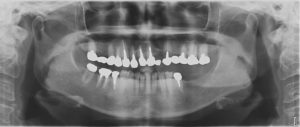

下の写真はインプラントを埋入する前のパノラマ写真です。

写真は左右反転して見て下さい!

こちらの患者様は左上2番のBrが入っていた所と、左上4番のBrの所を外してインプラントを埋入しています。

左上4番のBrの所は今まで両隣の歯が支台歯になっていたので負担がかかっていましたが、この負担を無くす為にインプラントを埋入しました。